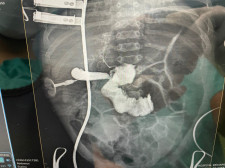

Procedimiento

Colangiograma Transoperatorio